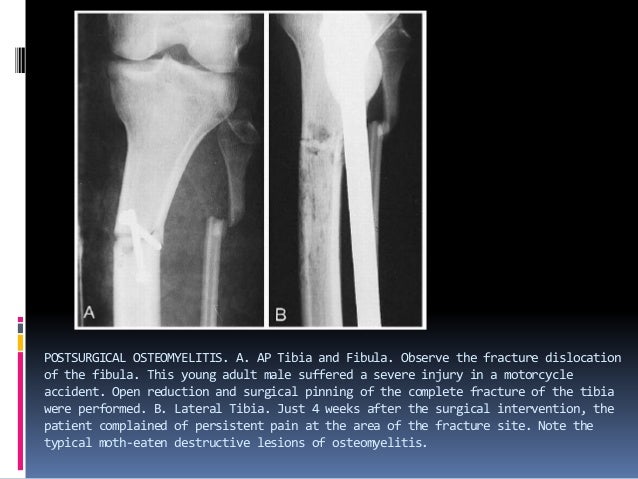

osteomyelitis 24 638, image source: www.slideshare.net